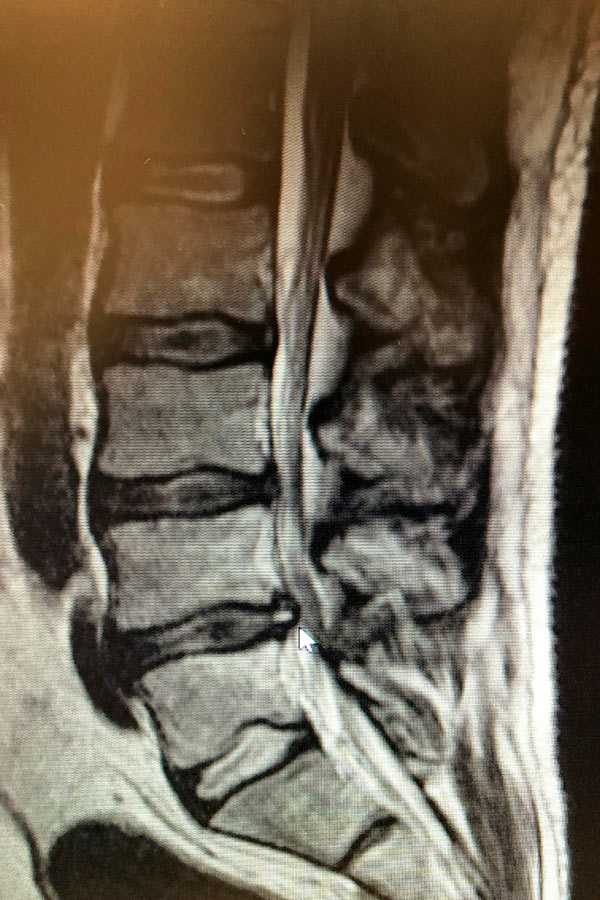

Hernia discal lumbar entre la 4ª y la 5ª vertebra con migración caudal

En la resonancia realizada se ver una liberación caudal por parte de la hernia, que comprime las raíces pasantes. Se detecta también un desgaste en un disco L5S1 desgastado, pero que no contiene ninguna hernia que pueda comprometer el tejido.